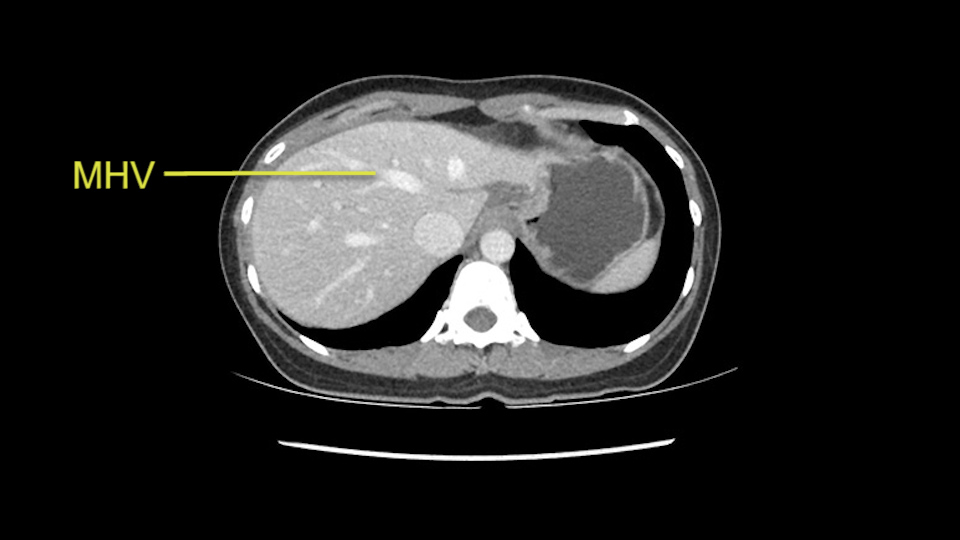

Anatomically, to plan for a left lateral segmentectomy, it’s relatively easy as far as liver surgery goes. I know that I'm going to be looking for the left hepatic vein which will be divided at some point either towards the end at the back near the vena cava or through the middle of the left lateral segment.

Preserve middle hepatic vein

The transection line will be a little more obvious. There’s a little patch of focal fat here in Segment 4b but we’ll describe the transection line probably through the mid portion of Segments 4a and b up to the top. Up at the top, the left hepatic vein can be taken. There’s a Segment 3 vein or the so-called falciform vein it’ll be rudimentary so I think we’ll be able to get around the left hepatic vein and leave the middle [hepatic] vein intact because it’s free of tumor.

Her vein, it looks like a combined middle and left hepatic vein, it may be encircled during the case as a whole common trunk but most probably it will not be a big deal because if it is okay to go with the left lateral resection, the vein or the left hepatic vein can be catched during the intraparenchymal dissection and can be controlled in that side.

The next step would obviously be the left hepatic vein mobilization. Once you lift the left lateral segment up, and you mobilize from the caudate lobe, you’ll find that you need to identify [Arantius’ canal] and ligate [Arantius’ canal], then only the left hepatic vein comes into view at the apex of the caudate lobe. In this particular case, because the hepatic venous plane is intact and its pretty free, it’s quite easy to ligate the left hepatic vein and staple it off. That would complete the devascularization of the tumor.

So in terms of planning on the surgery, I think there’s two clear options for this patient and that we’ll need to assess once we’re in the operating room. One option would be to do a Segment 3 resection. This tumor seems like it's hanging from Segment 3 so I think if we can get a good margin, that would be an option. Of course the other option is to do a left hepatectomy, preserving the middle hepatic vein, which is clearly not involved with the tumor.

The other option of course is to do an anatomical left hepatectomy. In that case, I will start mobilizing of course the left lobe and try to find the ligamentum venosum, take it down and go around the left hepatic vein. I think, importantly in these cases and in this case, as you can see in the venous phase, that’s clearly a moment to stop. Because the left hepatic vein is pretty close to the middle hepatic vein as sometimes it is so you may need to dissect a little bit the parenchyma on top of the left hepatic vein to be able to go around the left hepatic vein safely.